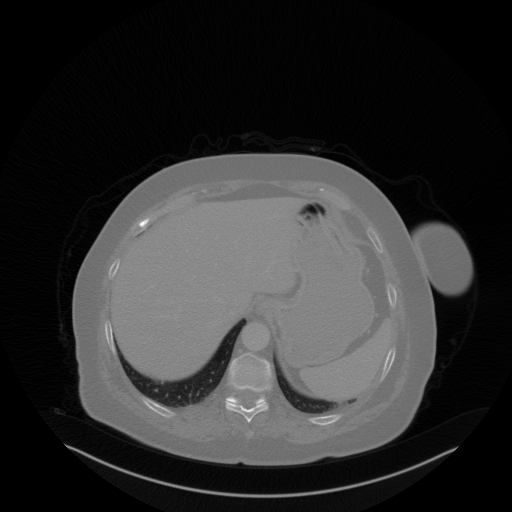

Image Grid

4Γ—3 grid: Rows show different image types (Original NATIVE, Reconstructed NATIVE, Original VENOUS, Generated VENOUS), Columns show windowing techniques (No Window, Lung Window, Mediastinum Window)

Original VENOUS CT scan

Full window (WL 1023.5, WW 4095 β†’ Low βˆ’1024, High +3071)